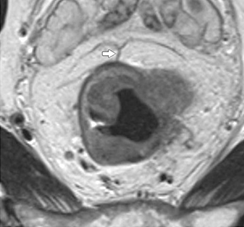

Определение локализации опухоли относительно переходной складки брюшины (полностью ниже/на уровне/полностью выше) выполняют в сагиттальных и/или аксиальных плоскостях (рис. 3).

Сагиттальная проекция является основной для оценки протяженности опухоли, ее положения относительно зубчатой линии (уровня верхнего края m. puborectalis) и переходной складки брюшины.